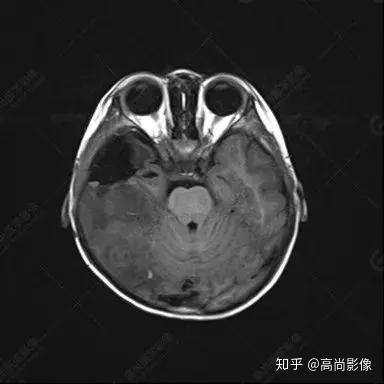

右側(cè)顳葉腫瘤切除術(shù)后(具體不詳):右側(cè)顳部骨質(zhì)不連續(xù)呈術(shù)后改變,右側(cè)顳葉術(shù)區(qū)見片狀長T1長T2信號影,F(xiàn)LAIR呈低信號;術(shù)區(qū)后方右側(cè)顳枕葉見一巨大占位性病變影,邊界欠清,大小約6.2×5.8×4.3cm(前后×左右×上下),信號不均勻,T1WI呈等稍低信號間雜少許高信號,T2WI呈高稍低混雜信號,DWI示部分病灶彌散受限,相應(yīng)ADC圖減低,磁敏感序列見部分呈極低信號,增強(qiáng)掃描可見明顯不均勻強(qiáng)化,鄰近硬腦膜及小腦幕增厚并明顯強(qiáng)化;另延髓右前方及右側(cè)橋小腦角區(qū)見一不規(guī)則形異常信號影,大小約3.2×1.3×3.7cm(左右×前后×上下),呈長T1稍長T2信號,F(xiàn)LAIR呈等信號,DWI未見受限,增強(qiáng)后明顯均勻強(qiáng)化,鄰近腦膜明顯強(qiáng)化。鄰近腦實質(zhì)及右側(cè)顳角明顯受壓;左側(cè)大腦半球未見局灶性信號異常,中線結(jié)構(gòu)稍左移。

右側(cè)顳葉腫瘤切除術(shù)后:現(xiàn)術(shù)區(qū)后方右側(cè)顳枕葉及延髓右前方占位,右側(cè)顳枕部硬腦膜及小腦幕明顯強(qiáng)化,結(jié)合既往影像資料,考慮為胚胎源性惡性腫瘤,如非典型畸胎樣/橫紋肌樣瘤(AT/RT)或原始神經(jīng)外胚層腫瘤(PNET)。

術(shù)后隨訪病理結(jié)果:非典型畸胎樣/橫紋肌樣瘤。

非典型畸胎樣/橫紋肌樣瘤(AT/RT) 是一種高度惡性中樞神經(jīng)系統(tǒng)腫瘤,臨床罕見,臨床表現(xiàn)無特異性,好發(fā)于 5 歲以下兒童,尤以 3 歲以下多見,在兒童原發(fā)性中樞神經(jīng)系統(tǒng)(CNS)腫瘤中占 1%~3%。該腫瘤體積一般較大,幕上大于幕下,有明顯的占位效應(yīng)。該腫瘤成分復(fù)雜,囊變、出血、壞死常見。因此 AT/RT信號混雜,囊性部分呈 T1WI低、T2WI高信號,增強(qiáng)后不強(qiáng)化;若瘤體出血,囊內(nèi)可見T1WI稍高信號、T2WI低信號,實性部分在 T1WI上呈混雜等、低信號,在T2WI 及 T2-FLAIR上呈混雜等高信號,增強(qiáng)掃描后大部分呈環(huán)形條帶樣明顯強(qiáng)化,中心壞死區(qū)不強(qiáng)化。另外,該腫瘤實性成分在DWI上呈高信號,說明腫瘤細(xì)胞核密集,水分子擴(kuò)散明顯受限,提示該腫瘤惡性程度高,容易復(fù)發(fā)及轉(zhuǎn)移。